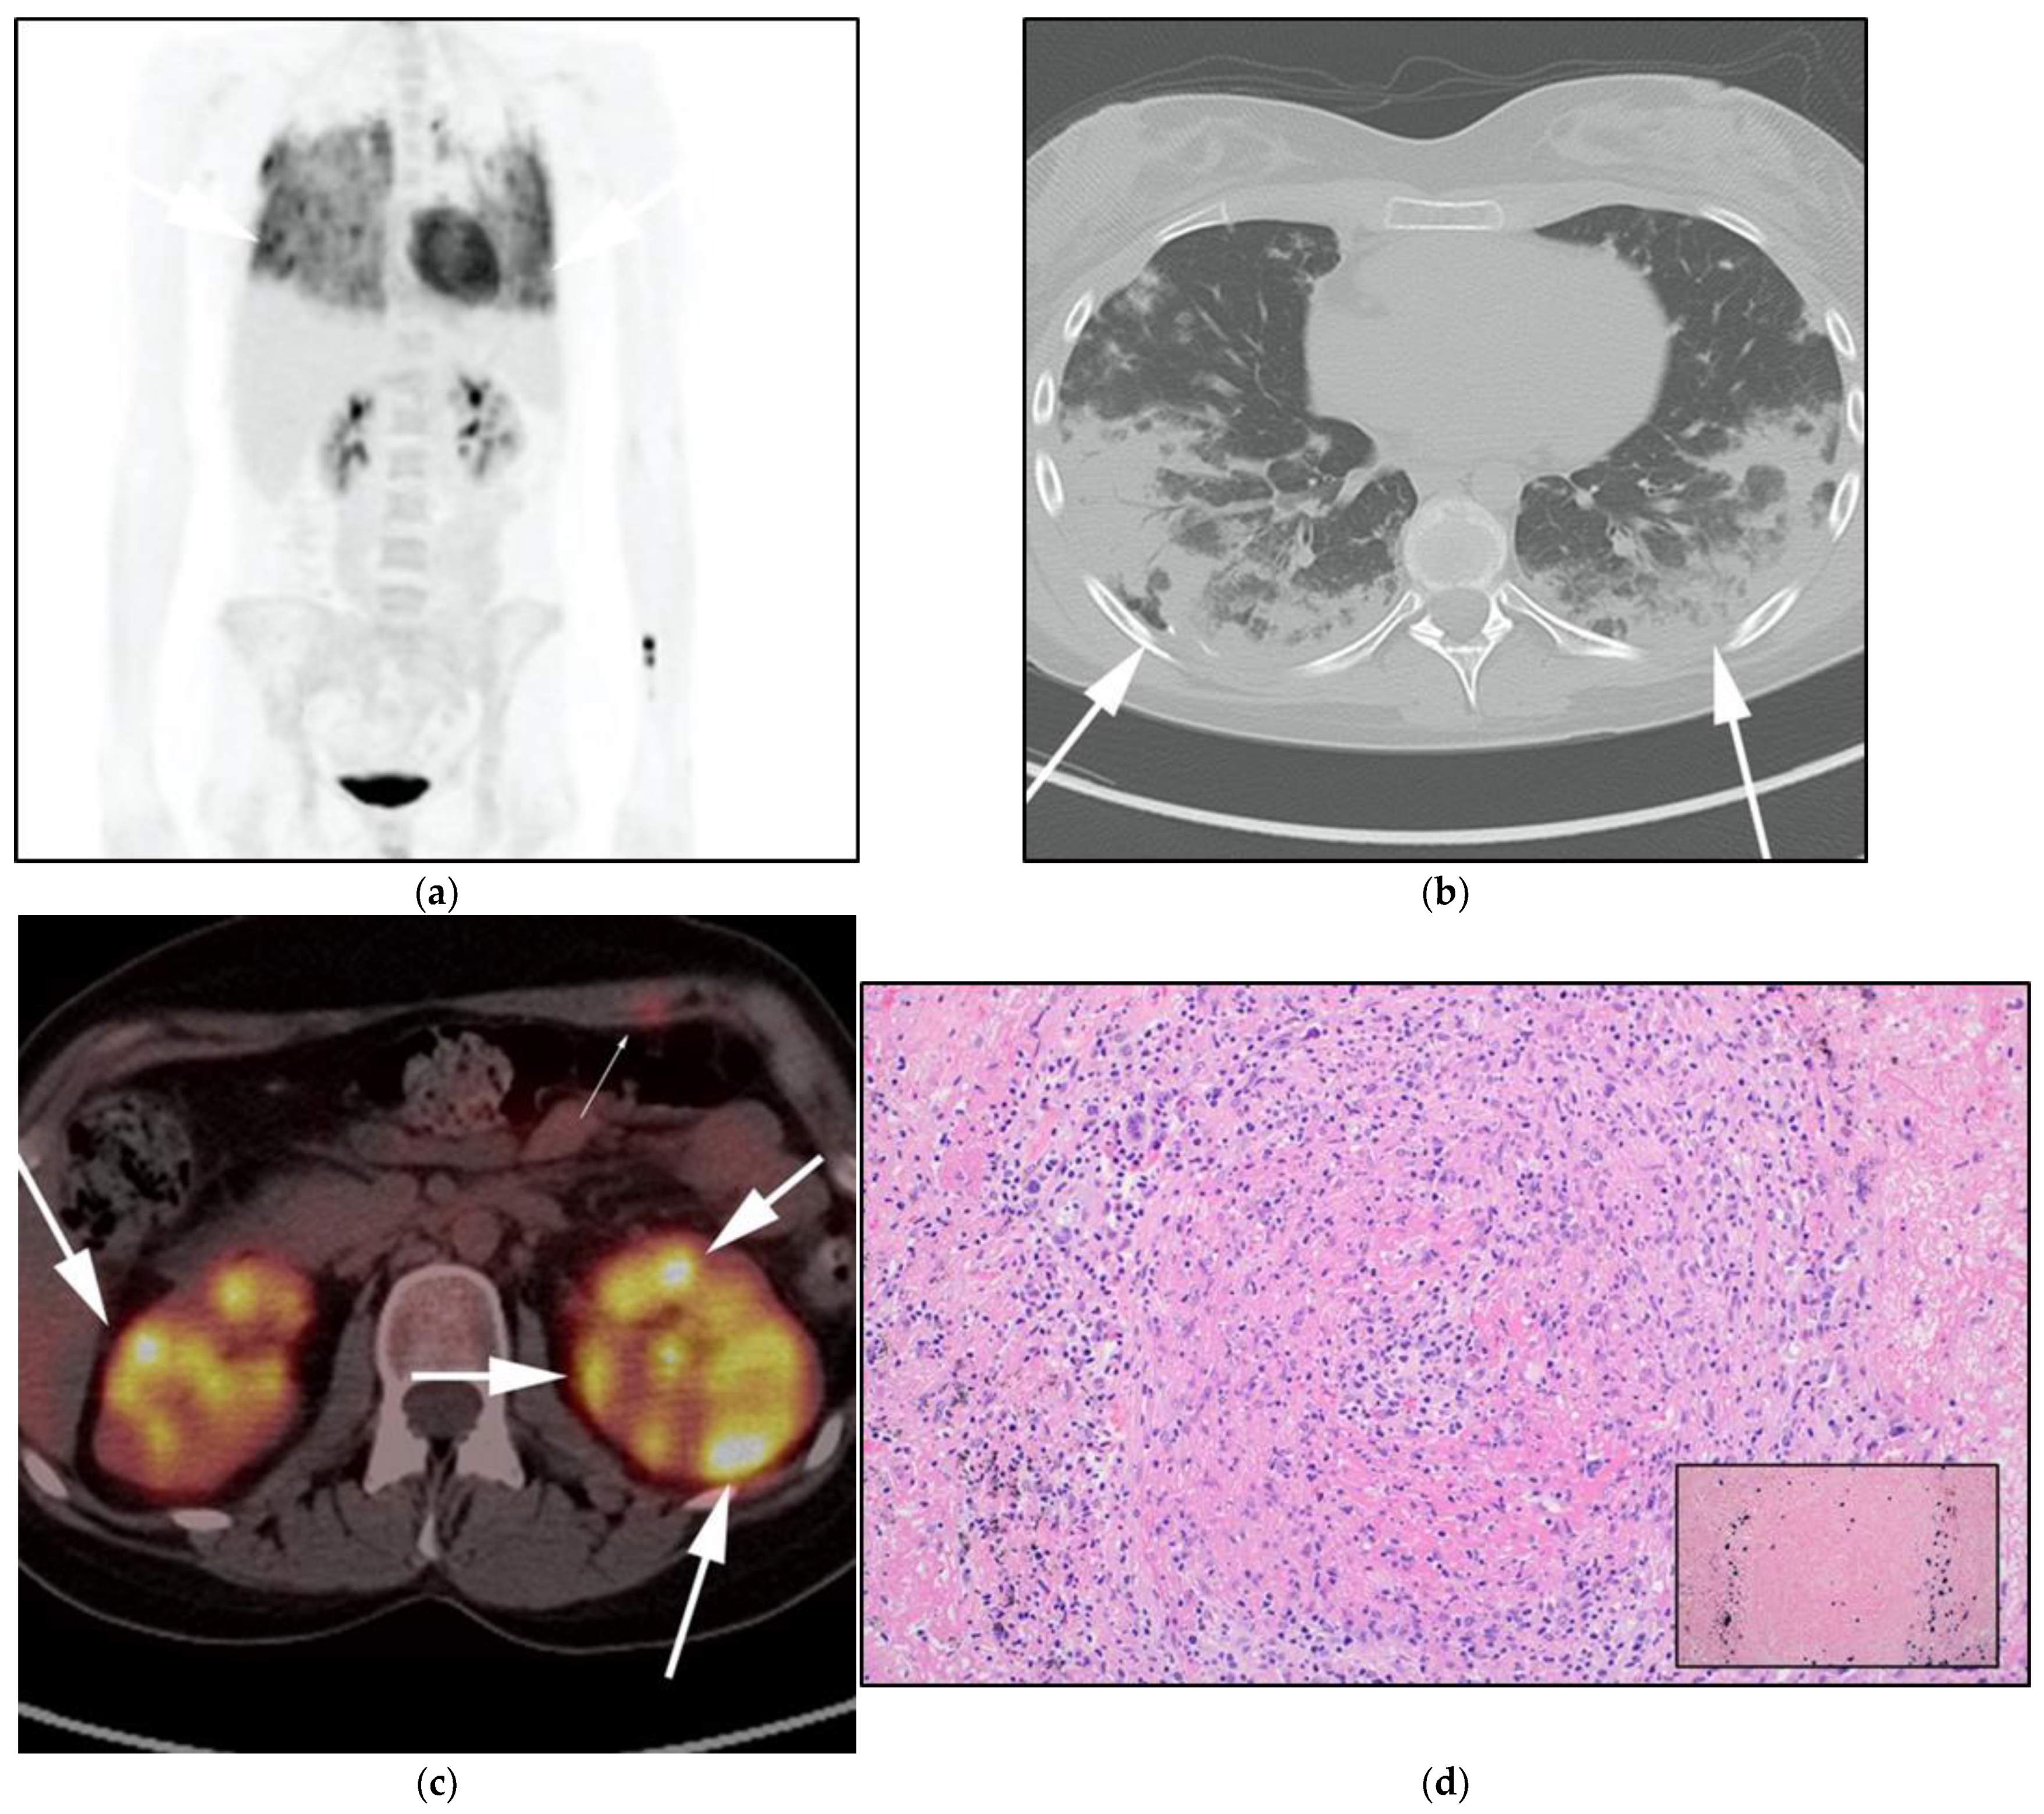

Figure 4.

A 30-year-old male with known history of autoimmune lymphoproliferative disorder since childhood. (a) Maximal intensity projection (MIP) FDG PET/CT image shows generalized hypermetabolic lymphadenopathy throughout the head, neck, chest, abdomen, and pelvis (white arrows). Note that splenic activity is not visualized (thin white arrow) because the spleen was surgically removed during childhood due to splenomegaly. (b) Axial FDG PET image shows hypermetabolic adenopathy within pelvis mainly about the bilateral pelvic side wall and external iliac nodes (white arrows). Lymph nodes often show little or only modest uptake, a clue, in addition to stability of nodal size and over multiple time points. Biopsy is the only method for definitive diagnosis. (c) H&E section of a lymph node shows highly proliferative paracortical expansion composed of small proliferative lymphocytes and immunoblasts with preserved lymphoid follicular architecture. There is sinus histiocytosis. (Original magnification 400×, H&E stain).

Once the diagnosis of ALPS is established, baseline and periodic follow-up CT scans should therefore be obtained to document the stability of lymphadenopathy and hepatosplenomegaly. 18F-FDG PET/CT may also be helpful because mild to moderate FDG uptake is typical of ALPS compared to the high FDG uptake characteristic of malignant lymphomas. By evaluating for areas of high FDG uptake, 18F-FDG PET/CT may help in the early detection of lymphoma transformation and demonstrate the best site for biopsy, when indicated [23]. Awareness of ALPS is pivotal because ALPS often requires long-term immunosuppressive therapies as opposed to chemotherapy that is standard for malignant lymphoproliferative disorders.